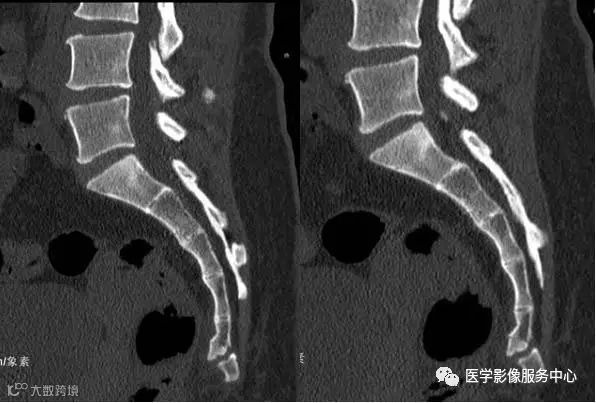

按不同的弯曲形态将其分为:均匀弯曲型、骶骨成角型、尾骨成角型、尾骨脱位型4种类型(见图1- 9),其中骶骨成角一般在S3、S4-5和S5部位,成角最大为70°。

图1 均匀弯曲型;图2 骶骨成角型(骶3);图3 骶骨成角型(骶4-5);图4 骶骨成角型(骶5);图5尾骨成角型(尾1);图6 尾骨成角型(尾1-2);图7 尾骨成角型(尾2-3 );图8 尾骨脱位型;图9尾骨脱位型。